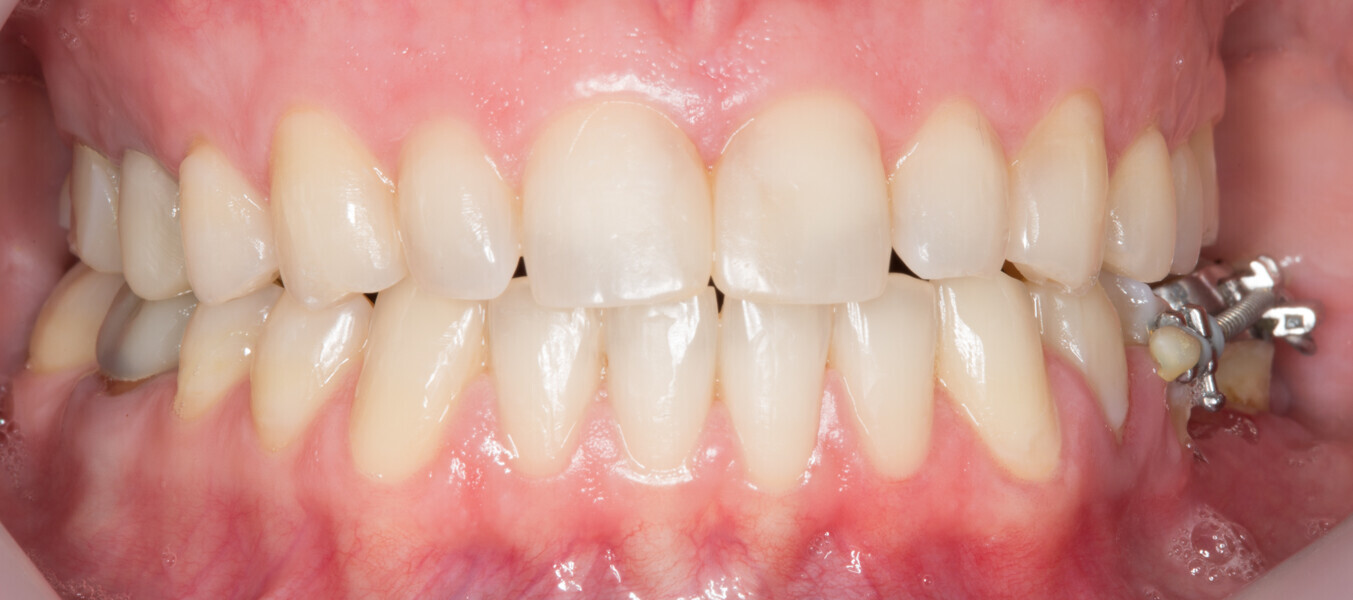

Fig. 1: Initial clinical situation.